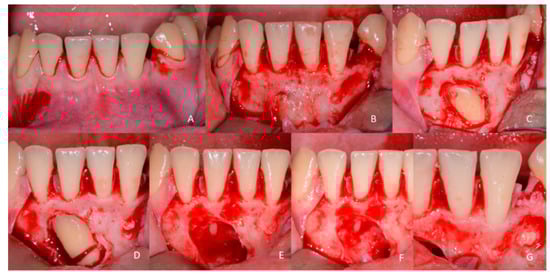

1.1. Case Number 1

1.2. Case Number 2

1.3. Case Number 3